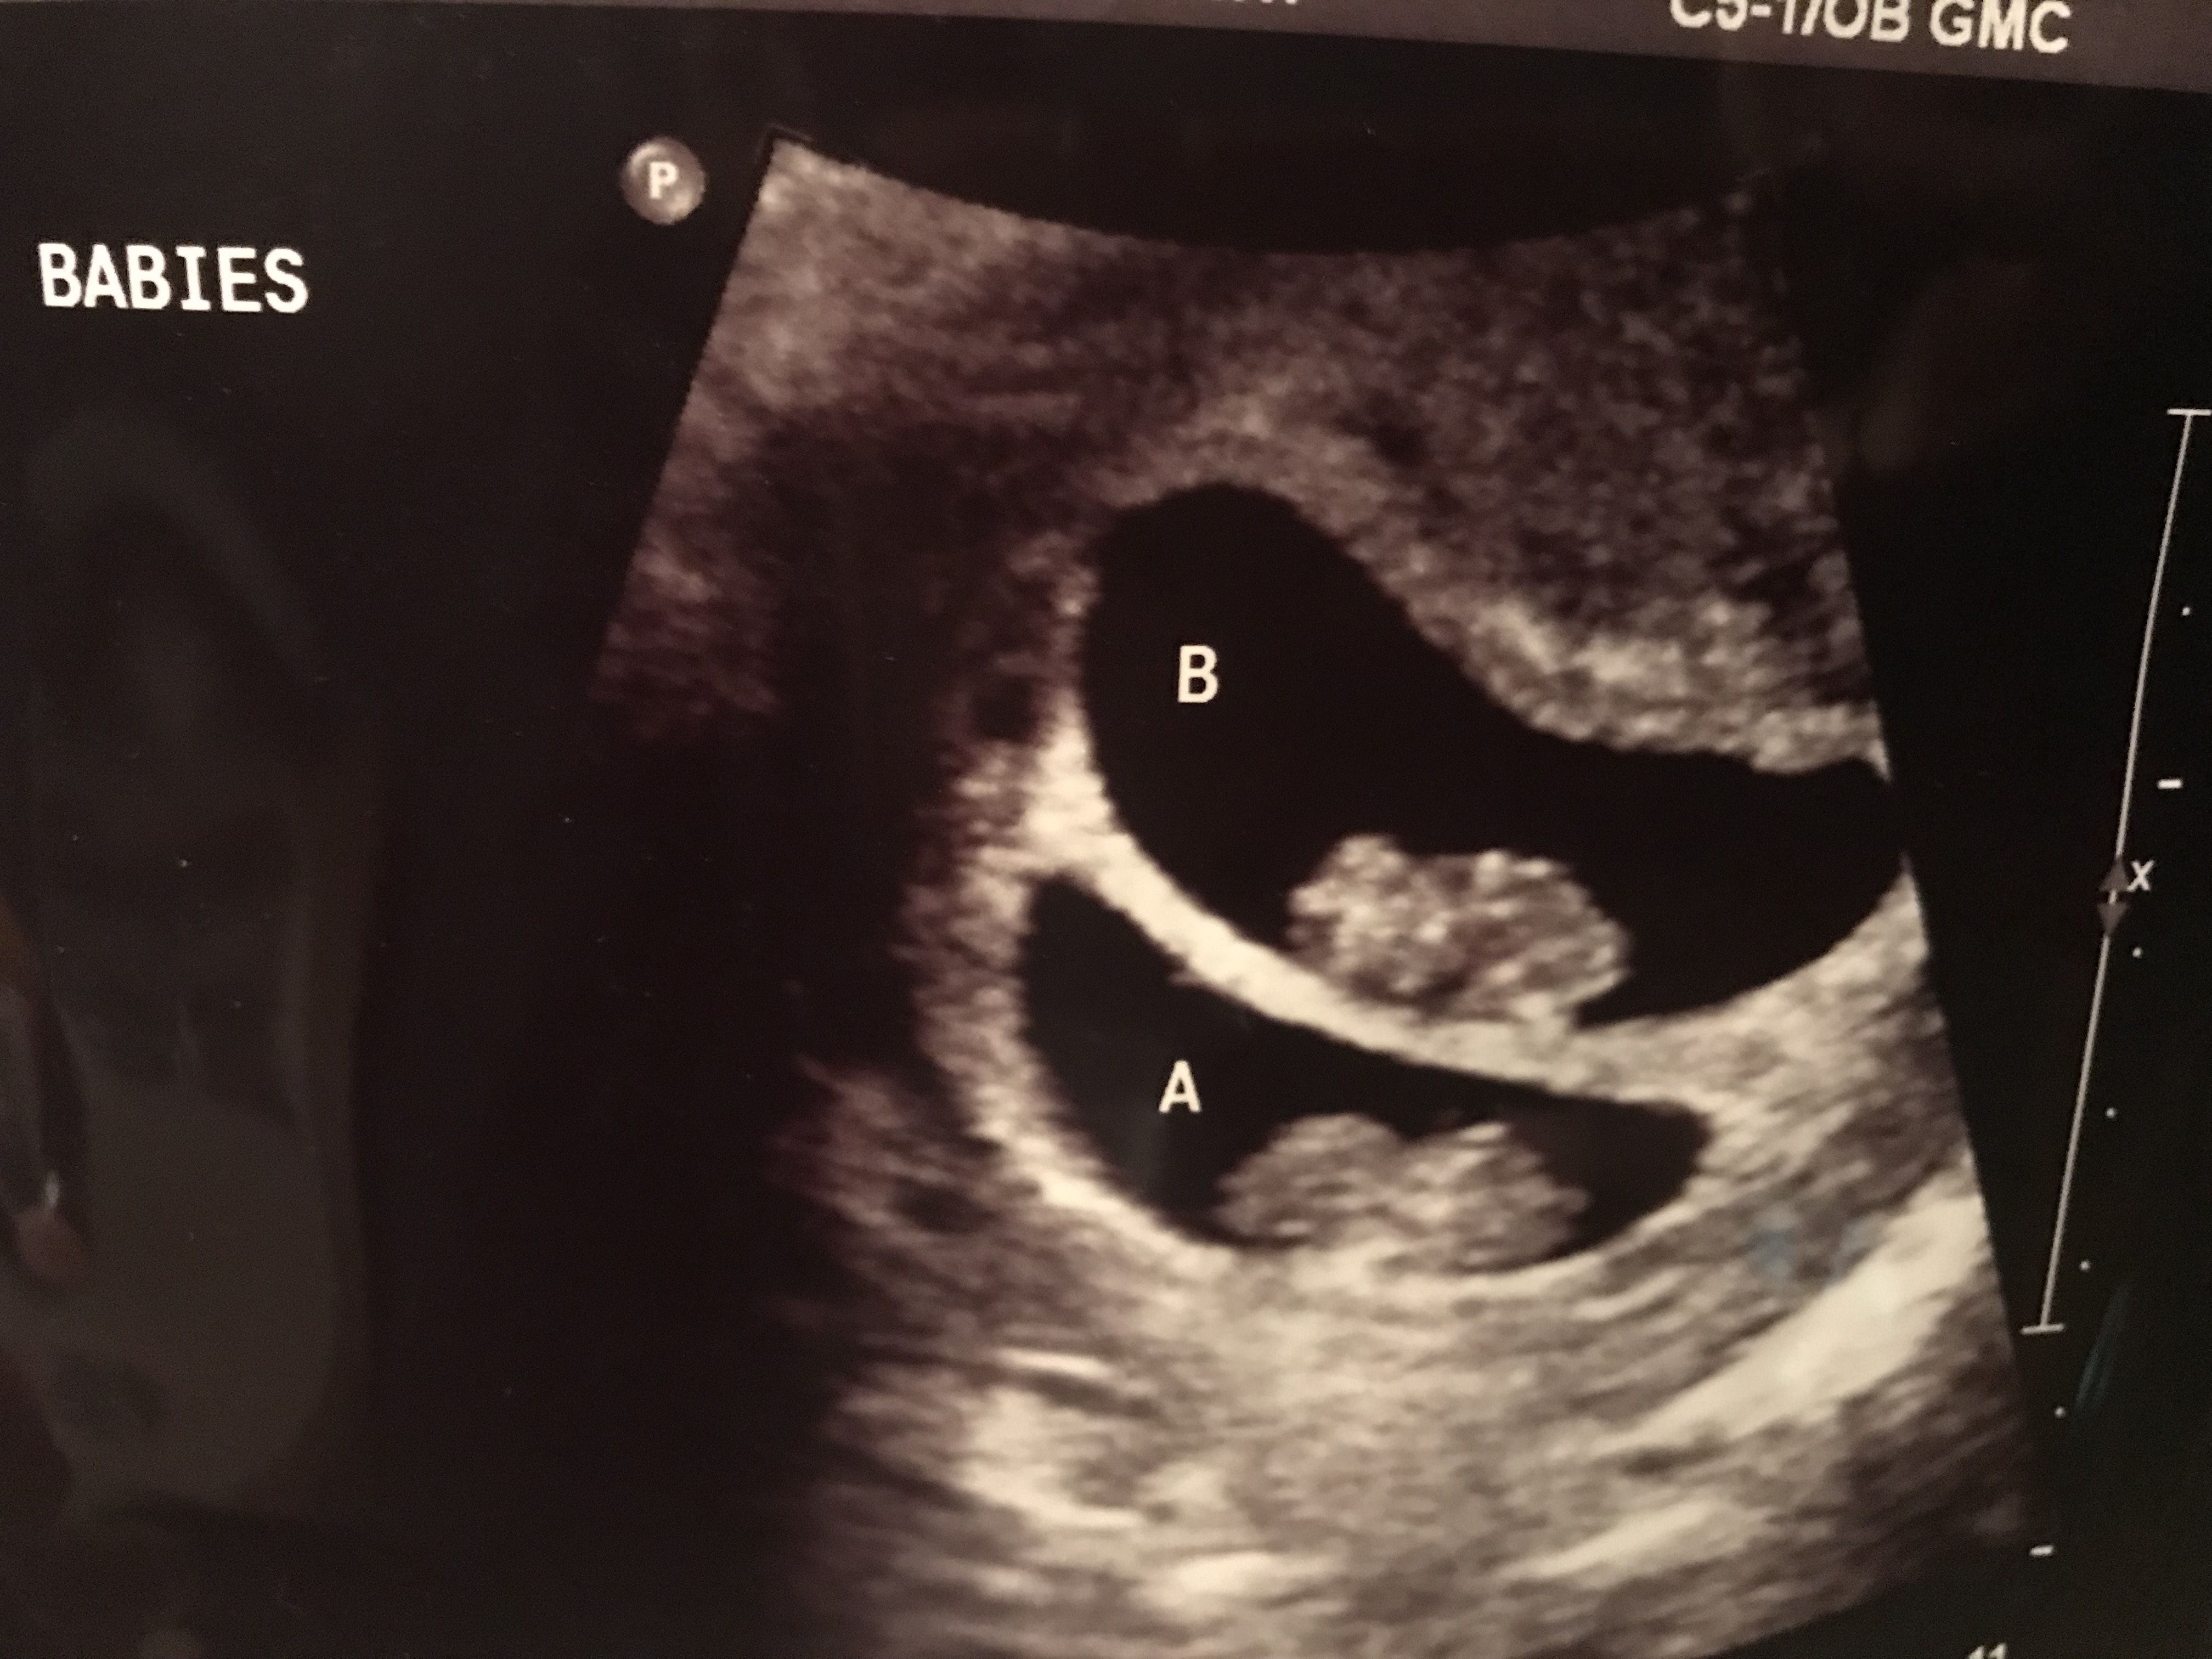

Ultrasound Photos of 9 Weeks Pregnant With Twins